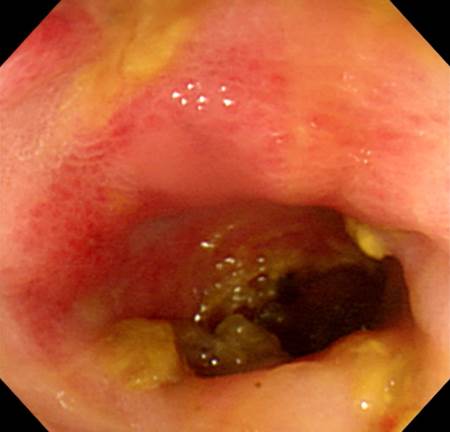

[CMV colitis (s/p PBSCT for leukemia)]